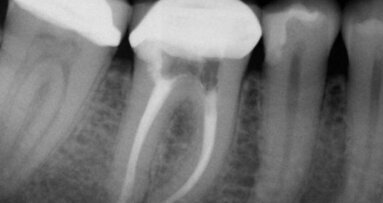

Rozpoznano: grupę II wg Majewskiego, grupę A3 wg Eichnera, a wg Galasińskiej-Landsbergerowej – klasę II zarówno w szczęce, jak i w żuchwie. W badaniu klinicznym wykazano nieprawidłowości, które w sposób istotny mogłyby wpłynąć na końcowy efekt leczenia i wymagały przygotowania ortodontycznego przed przystąpieniem do docelowej rekonstrukcji implantoprotetycznej. Pacjent został skierowany na konsultację do ortodonty, gdzie stwierdzono przedwczesną utratę zębów 14, 36, 46, zgryz urazowy tet-a-tet na 12, 42, szparowatość wtórną między 43 i 44 oraz 33 i 34, mezjoinklinację 15, 37, 47, asymetrię łuku górnego i dolnego, pogłębienie zgryzu, stłoczenie dolnych siekaczy niewielkiego stopnia oraz spłaszczenie kształtu łuku dolnego.

Założono 2 aparaty stałe (AS). Leczenie ortodontyczne trwało ok. 14 miesięcy. Po roku od rozpoczęcia leczenia założono implanty w miejsce brakujących zębów 14, 46 i 36. Implantację

wykonano zgodnie z ogólnie przyjętą procedurą, przy czym do implantów dokręcono

od razu śruby gojące (tzw. Gojenie otwarte). Po zdjęciu górnego AS pacjentowi przyklejono retainer 13-33 i wykonano płytkę Schwartza, którą miał użytkować do czasu wykonania odbudowy protetycznej. W łuku dolnym wykonano retencję stałą w odcinku 35-45. Wykonanie retencji skojarzono z osadzeniem implantokoron 36 i 46.

Wyciski do implantokoron zostały pobrane przed zdjęciem dolnego AS, metodą pick-up. Wycisk do implantokorony 14 wykonano 2 miesiące po zdjęciu górnego AS, również metodą pick-up. Do wykonania wycisków użyto masy Impregum w systemie Pentamix.

Rejestracja i przeniesienie zwarcia przebiegało zgodnie z obowiązującymi standardami.

Wykorzystano artykulator Stratos 200 z łukiem twarzowym (Ivoclar Vivadent). Część metalową koron protetycznych wykonano z tytanu metodą odlewniczą, a olicowanie z porcelany Titankeramik (Vita). Łączniki protetyczne (Ti tanaufbau) dokręcono kluczem dynamometrycznym z siłą zalecaną przez producenta. Głowy śrub łączników zabezpieczono silikonem. Implantokorony osadzono na temp-bond (Tarnow). Uzyskano poprawne kontakty zwarciowe.